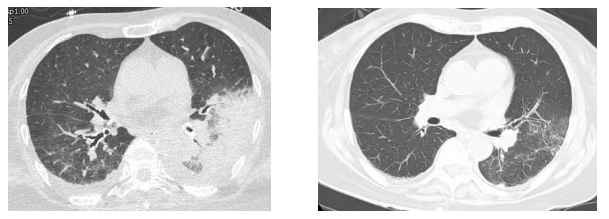

三、胸CT有哪些特点?

胸CT以炎性病变始于单侧肺下叶多见,加重后累及双侧肺叶,上下肺均可受累,主要表现为大片状实变影,可合并小片状磨玻璃影、结节影,以胸膜下分布为主,可见“支气管充气征”“细网格征”“晕征”,常伴胸腔积液,可伴淋巴结肿大。